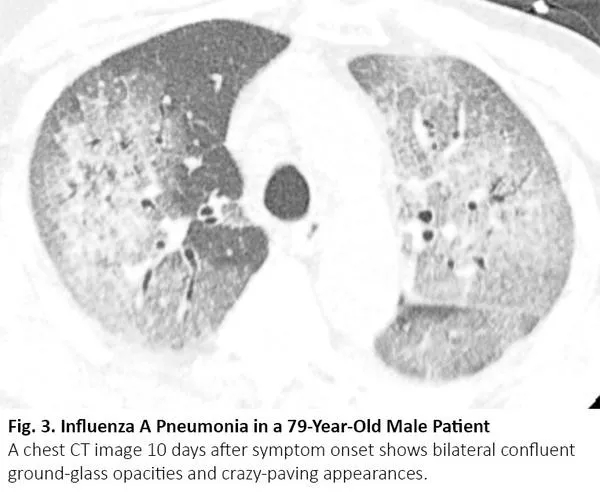

肺癌患者在病程中可能出现与COVID-19类似的CT异常,但这些异常是由于其他原因,如病毒性肺炎、癌症复发和间质性肺病。病毒性肺炎,特别是流感肺炎,在胸部CT上可表现为双侧磨玻璃样影和实性病变,胸部CT上位置分布相似10(图3),秋冬流感高发时,利用放射学检查结果来鉴别二者可能有问题。COVID-19 CT比流感肺炎CT更多见小叶间隔增厚及圆形阴影(典型肺周分布),但肺结节和树芽征相对更少。11

图3. 流感肺炎